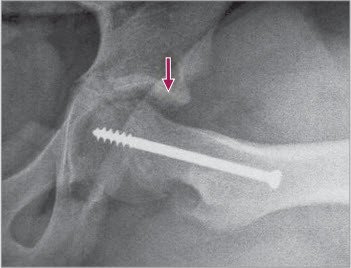

nach offener Reposition

4 Postoperatives seitliches Bild nach offener Reposition. Der Pfeil zeigt (vorne) die reponierte Kalotte unter leichter Verkürzung des Schenkelhalses, vergleiche präoperatives Bild Abb 2